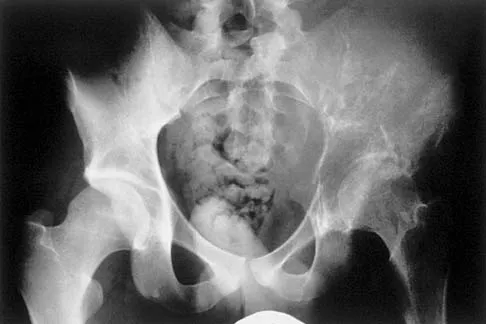

Figure 2a shows the radiograph of a 48-year-old man who was involved in a motorcycle accident. A CT scan is shown in Figure 2b. The patient underwent pelvic angiography for persistent hypotension despite resuscitation. What vessel is most likely to be injured?

Explanation

The pelvic injury is a severe anterior-posterior compression III or Tile C injury. The vessel most likely injured is the superior gluteal artery, but several arterial bleeding sources are likely. Vertical shear injuries can also injure this vessel, but it is much less common. When arterial injury follows a lateral compression injury, it is usually related to injury of a more anterior vessel like the obturator artery or a branch of the external iliac artery. O'Neill PA, Riina J, Sclafani S, et al: Angiographic findings in pelvic fractures. Clin Orthop 1996;329:60-67.